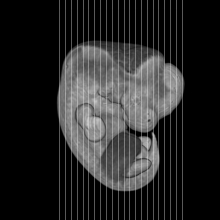

MRI Slice Selector

Mouse: click on a line below to select a view

Finger: tap a line below with a very light touch